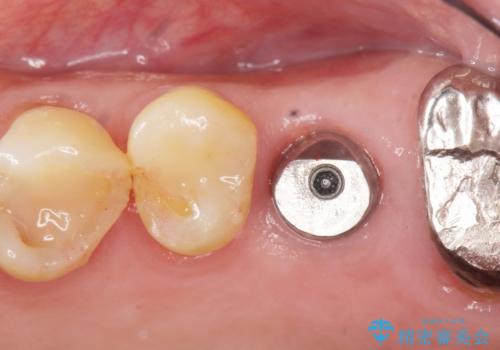

奥歯のインプラント ソケットリフト 60代男性

- 奥歯のインプラントをご希望し、来院された患者様です。

精査したところ上顎骨の厚みが薄かったため、ソケットリフト(上顎洞底挙上術)を併用してインプラント治療を行いました。

審美的・機能的な仕上がりに喜んで下さいました。

また、半年という比較的短期間でインプラント治療が終わったことにもご満足頂けました。

インプラントの種類:スプライン ツイスト (保証期間:5年)

クラウンの種類:ベレッツァクラウン (オールセラミック)

固定様式:セメント固定